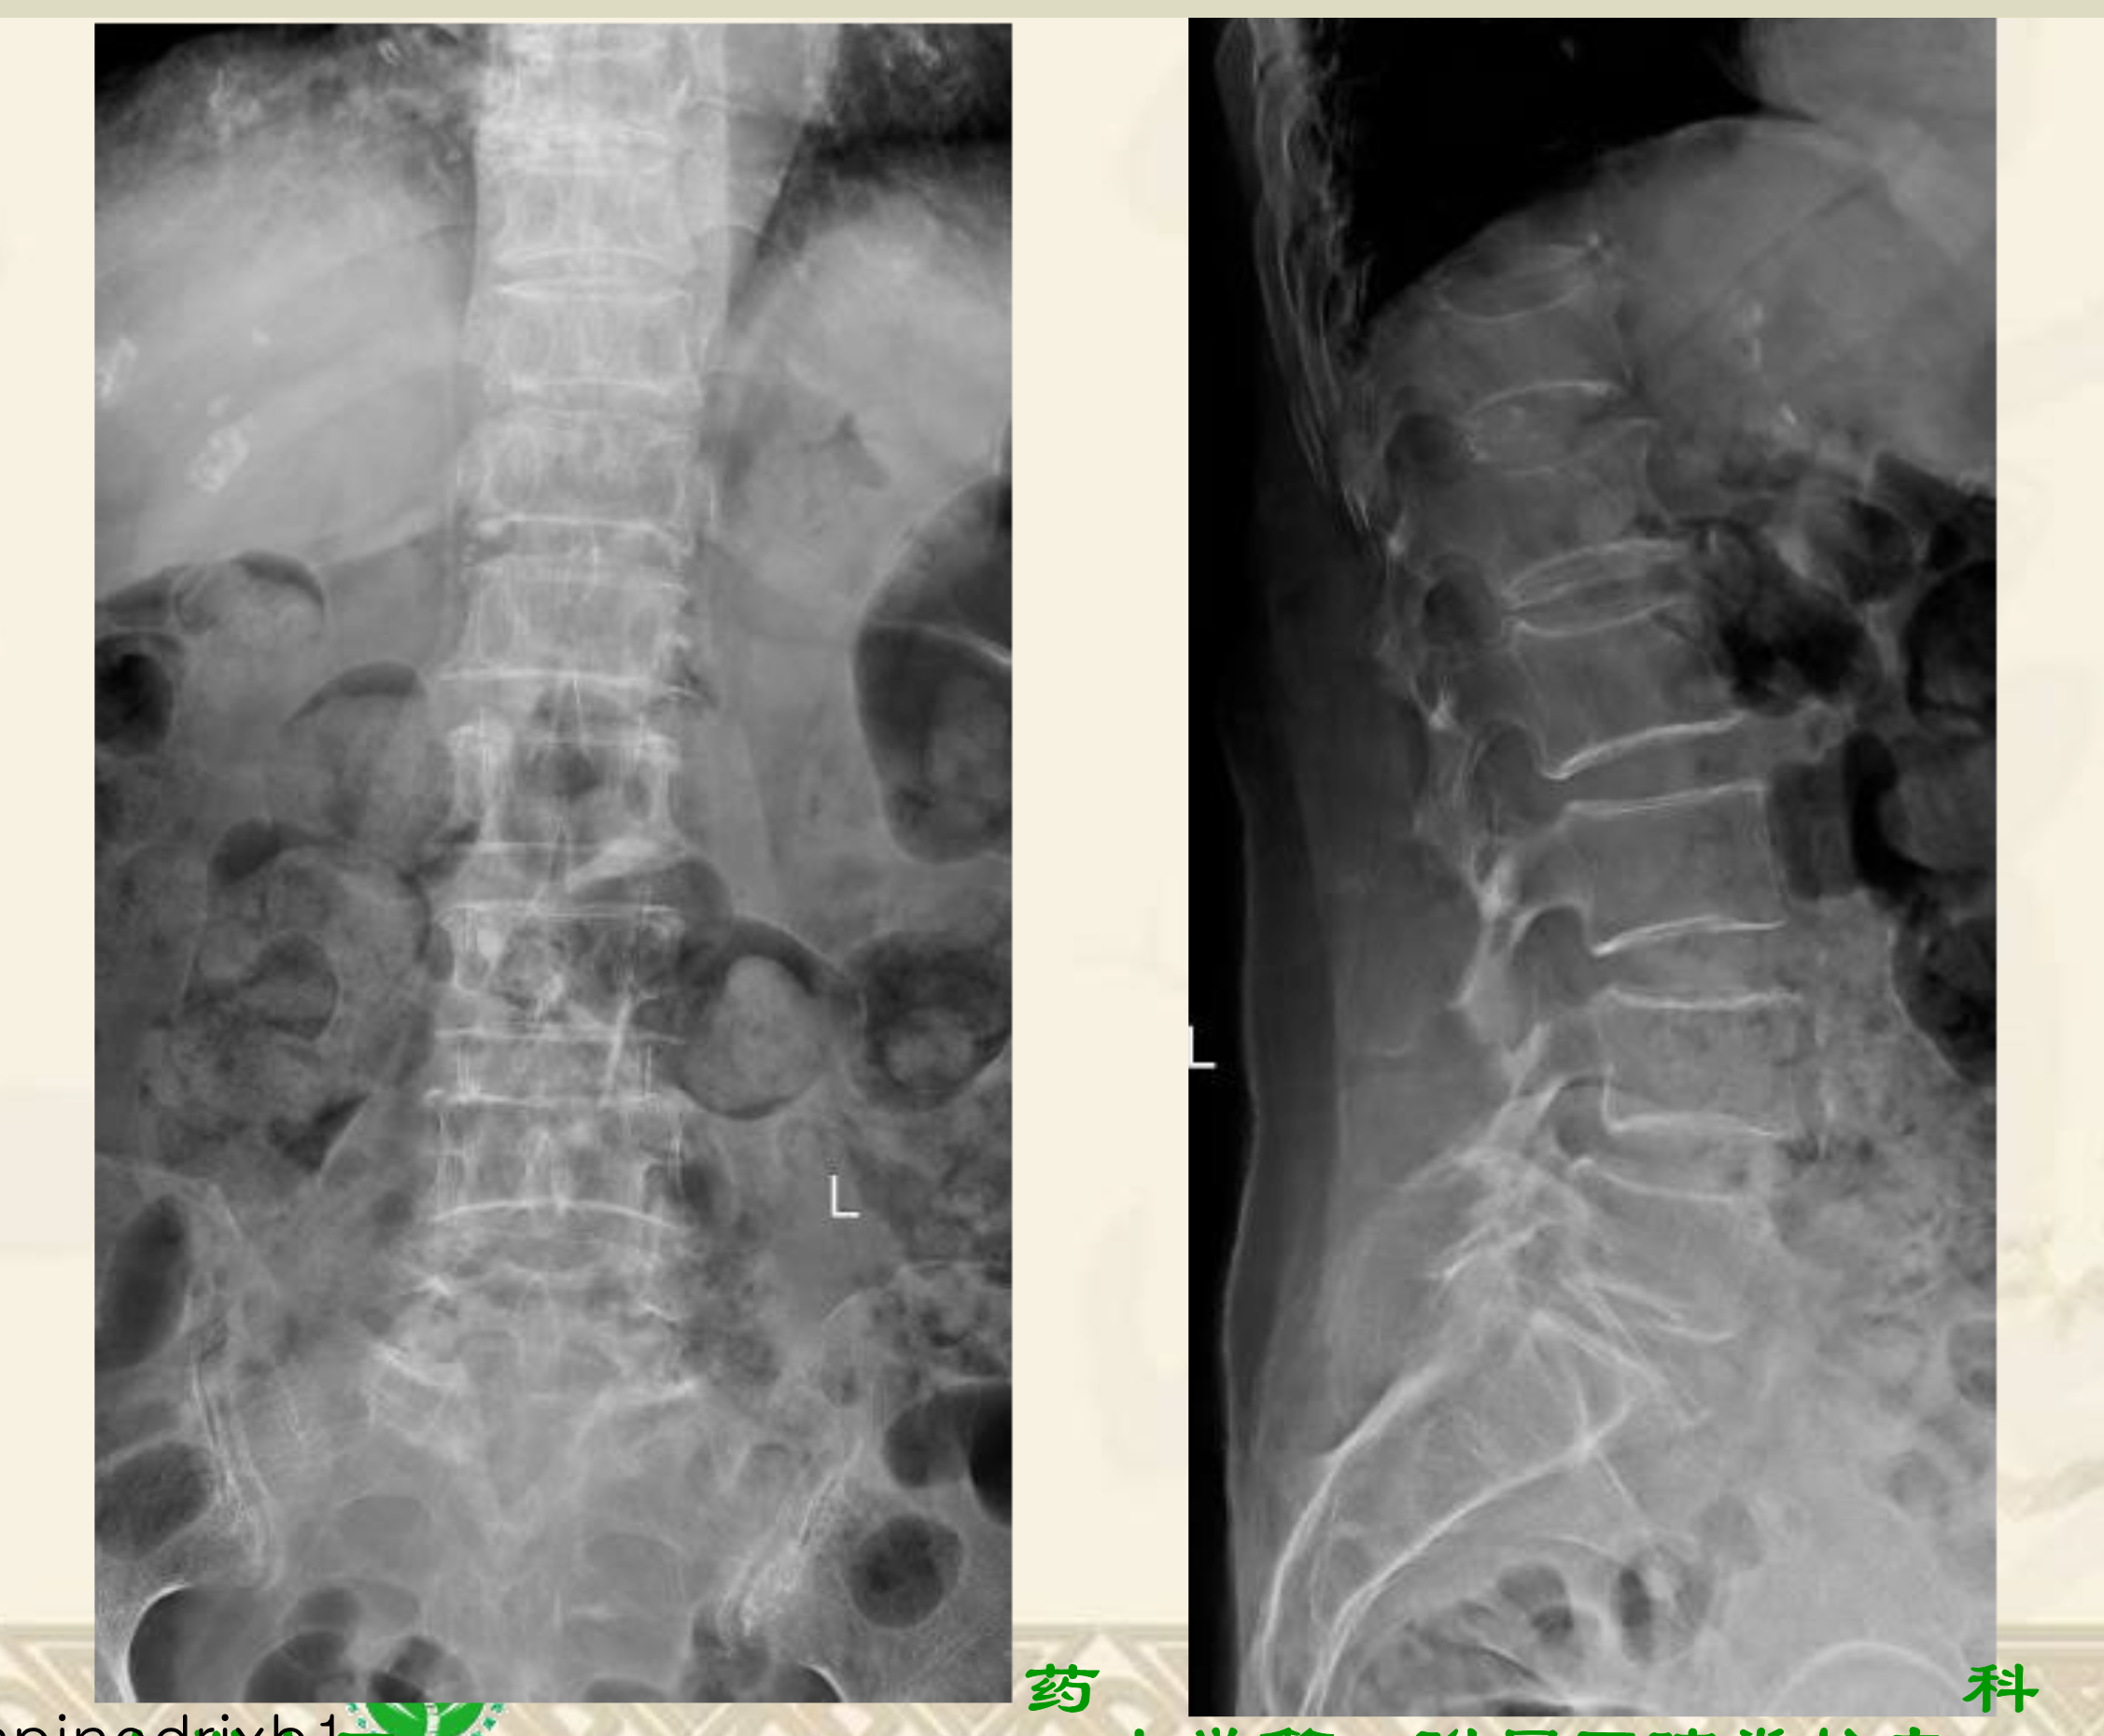

术前X线

术前MRI

术前CT